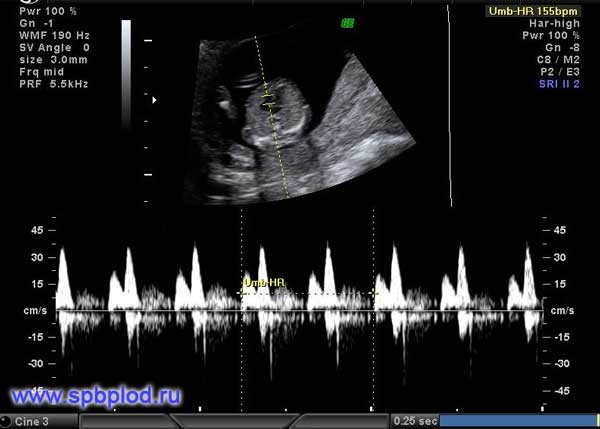

Помимо измерения толщины воротникового пространства и оценки носовой кости, предложено еще несколько маркеров: оценка кровотока через трикуспидальный клапан сердца и через венозный проток, а так же измерение лицевого угла плода. Оценка данных маркеров требует от врача высокой квалификации, и возможна только после получения международной сертификации по каждому маркеру.

Обычно кровь в сосудах плода течет в одном направлении: от сердца к периферическим сосудам. При наличии хромосомной патологии у плода или пороков сердца направление тока крови может изменяться, и в некоторые фазы сердечного цикла кровь начинает течь обратно к сердцу.

Регистрация кровотока через трикуспидальный клапан сердца и через венозный проток (этот небольшой сосуд есть только у плодов, в периоде новорожденности кровоток в нем прекращается, и он закрывается) позволяет выявить до 65% плодов с болезнью Дауна. У 1-3% нормальных плодов мы также можем увидеть обратный кровоток в венозном протоке или через трикуспидальный клапан, поэтому эти признаки должны оцениваться в комплексе с другими данными ультразвукового исследования.

Патологический обратный кровоток через трикуспидальный клапан сердца плода в 12 недель беременности